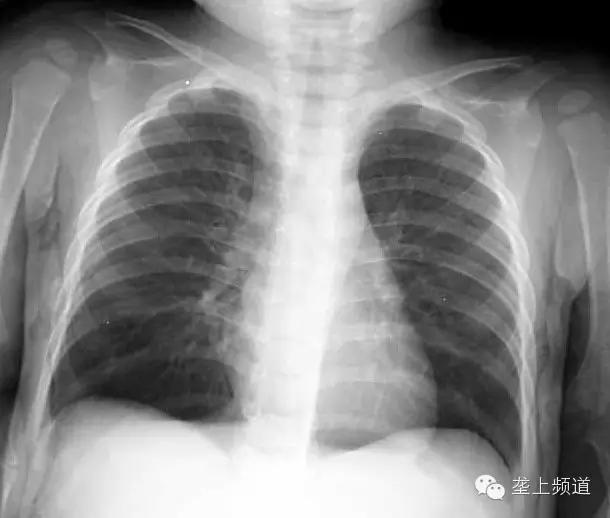

女婴将瓜子吸入支气管 右肺比左肺

6月15日,1岁女婴总是咳嗽喘气,吃药不见好转,扁桃体逐渐肿大。到医院一查,发现右肺含气量比左肺足足大了近3倍,几乎占满右侧胸腔,右支气管内还藏有一颗瓜子。